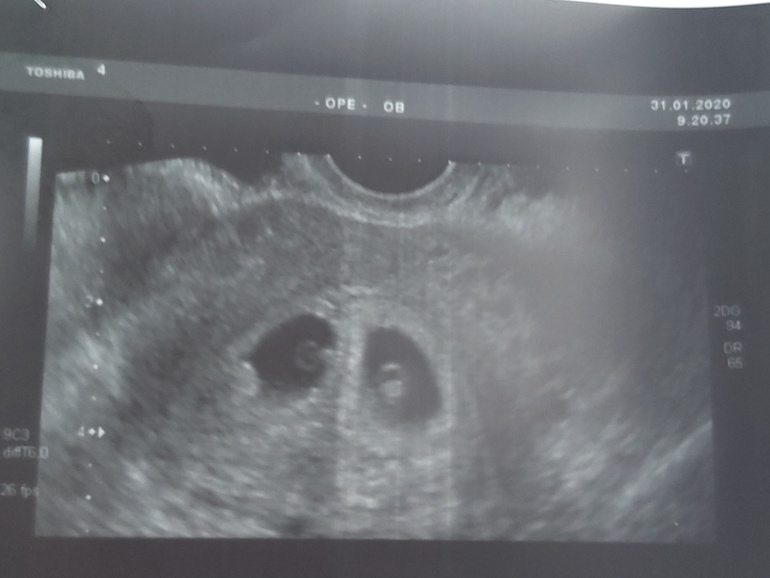

сделала узи на нормальном аппарате креветочки мои сладенькиеееееееее!

пя отличаются по размеру, но так было изначально 4.3 и до 5мм, через неделю 10 и 12 мм ктр тоже разный 2.9 и 4.5 мм

увидела как пульсируют сердечки моих крошечек! 91 и 95 чсс читала, что при двойне это нормальная чсс